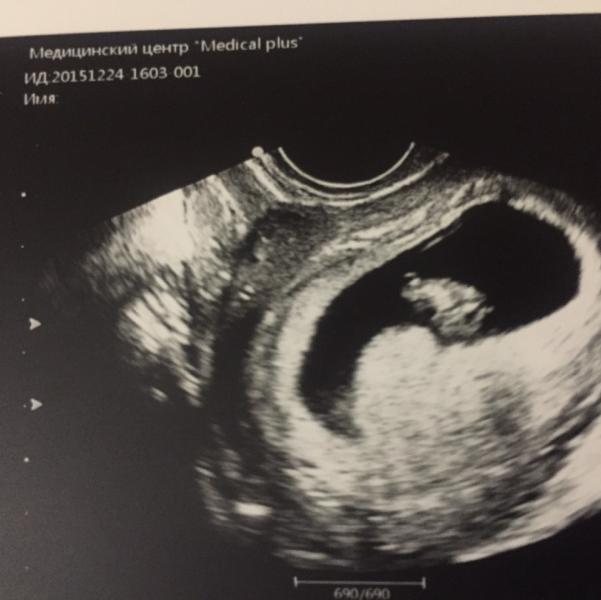

Ура! Наконец-то сегодня услышали сердечко нашего малыша! Он ещё совсем крохотный, и немного отстаёт по размерам, но Г сказала - догонит ещё))

Итак сегодня ровно 10 акушерских недель и 8 эмбриональных (по размерам)😊 и мы счастливы😍

А сердечко у нас 130 ударов в мин))